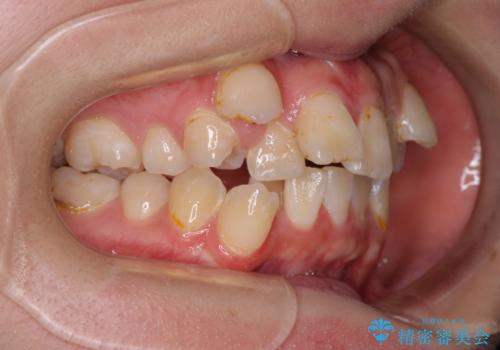

転位歯や埋伏歯などの難易度の高い抜歯矯正治療

- 八重歯や埋伏している奥歯など、多くの難しい問題を抱えている患者様です。

重度叢生のため、大臼歯をしっかりと咬合させるために、下顎は左右第二小臼歯を、上顎は前歯部の叢生を解消するために左右第一小臼歯を抜歯し、口元の突出感を改善するために、上顎大臼歯が前方に移動しないようにするために、補助装置による架強固定を行うこととしました。